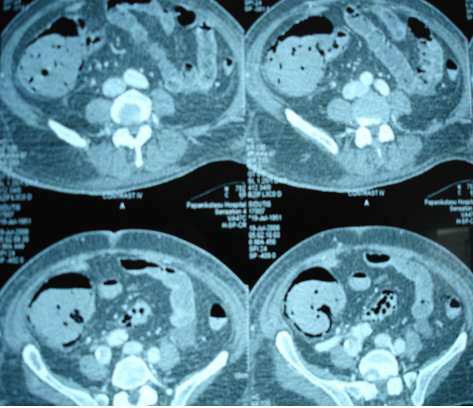

Multiple hepatic metastases — Absolute contraindication for cytoreductive surgery (Courtesy Dr. V. Penopoulos)